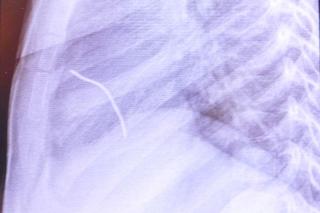

Pięciocentymetrowy kawałek metalowego drutu wystrzelił spod ostrza kosiarki jak z procy, przeszedł przez klatkę piersiową stojącego kilka metrów obok Przemka (5 l.) z okolic Opoczna (woj. łódzkie) i utkwił w jego sercu. Gdyby przebił je na wylot, chłopiec wykrwawiłby się na śmierć - Miał mnóstwo szczęścia – mówią lekarze z łódzkiego szpitala Centrum Zdrowia Matki Polki, którzy usuwali ciało obce z jego organizmu.

Stan chłopczyka błyskawicznie się pogarszał. Karetka przewiozła go do szpitala w Opocznie, gdzie lekarze ustalili, że w jego serduszku tkwi metalowy przedmiot. Zaczęła się dramatyczna walka z czasem, bo liczyła się każda minuta. Helikopterem Lotniczego Pogotowia Ratunkowego przetransportowano Przemka do specjalistycznego szpitala Centrum Zdrowia Matki Polki. Tu natychmiast trafił na blok operacyjny.

- Zabieg trwał około półtorej godziny – mówi Marek Kopala, ordynator Kliniki Kardiochirurgii. - Nie był specjalnie skomplikowany, natomiast chłopiec miał dużo szczęścia. Okazało się, że drut wbił się w serce i tam się zatrzymał. Gdyby przeleciał na wylot, najprawdopodobniej doszłoby do wykrwawienia i tego mógłby nie przeżyć.